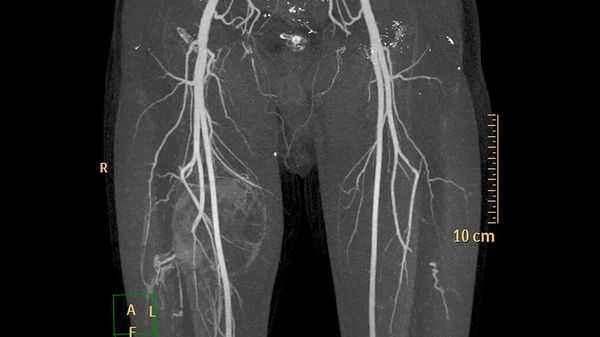

Врожденные ангиодисплазии (синдром Паркса-Вебера-Рубашова) - характеризуются наличием патологических соустий (фистул) между артериями и венами.

Артериовенозные соустья часто бывают множественными, имеют разнообразный калибр и форму. В зависимости от диаметра различают макрофистулы, заметные невооруженным глазом, и микрофистулы, которые выявляются только при микроскопическом исследовании тканей конечности.

Патологические соустья чаще располагаются в зоне бедренной, ветвей подколенной артерии, а также по ходу большеберцовых артерий. Интенсивный сброс артериальной крови через артерио-венозные свищи ведет к повышению давления крови в венах.

Клиническая симптоматика обусловлена нарушениями регионарного кровообращения и центральной гемодинамики. Конечность удлинена на 3-8 см, мягкие ткани ее гипертрофированы. Удлинение конечности обусловлено продуктивной перестройкой костной ткани из-за усиленной васкуляризации эпифизарных линий.

Характерно наличие варикозно расширенных поверхностных вен на нижней или верхней конечности. Их появление связано с высокой венозной гипертензией вследствие заброса крови из артерии. Стенки вен плотноэластической консистенции, с трудом сжимаемые. Расширенные вены не исчезают после придания конечности возвышенного положения. Иногда при осмотре над ними определяется пульсация.

Наиболее важным методом диагностики врожденных артериовенозных свищей является ангиография. Различают прямые и косвенные ангиографические признаки артериовенозных свищей Наличие на ангиограммах контрастированного соустья или сосудистой полости, сообщающейся с артерией и веной, относят к прямым признакам. Косвенно о наличии свища свидетельствуют одновременное контрастирование артерий и вен, расширение просвета приводящей артерии, обеднение сосудистого рисунка дистальнее расположения артериовенозного свища.